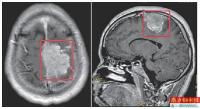

男子穿人字拖走几步就掉 近6厘米脑膜瘤在作怪

今年30出头的小王(化名),平时很爱穿人字拖,可就在去年底,小王穿起人字拖来开始不得劲了——人往前走了,人字拖却还在原地,每走几步右脚就夹不住拖鞋了,脚底还有麻木感。这种情况持续了几个月,小王的症